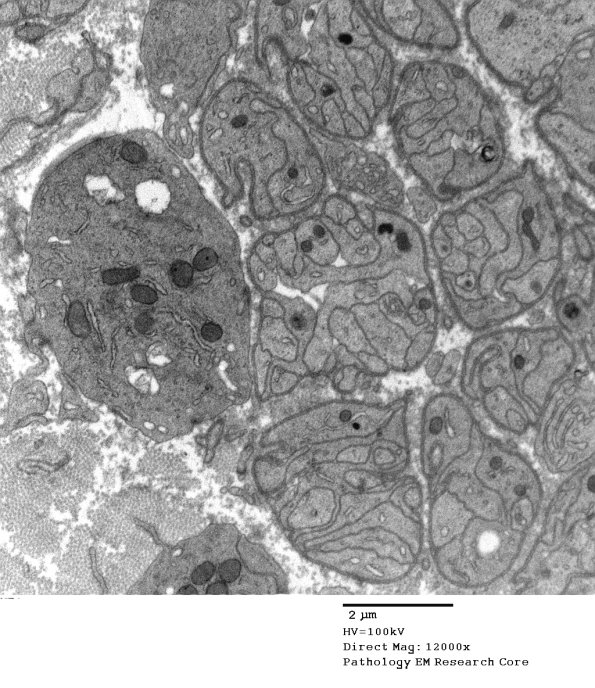

Schwann cells form bands of Büngner once axons degenerate. (electron micrographs)